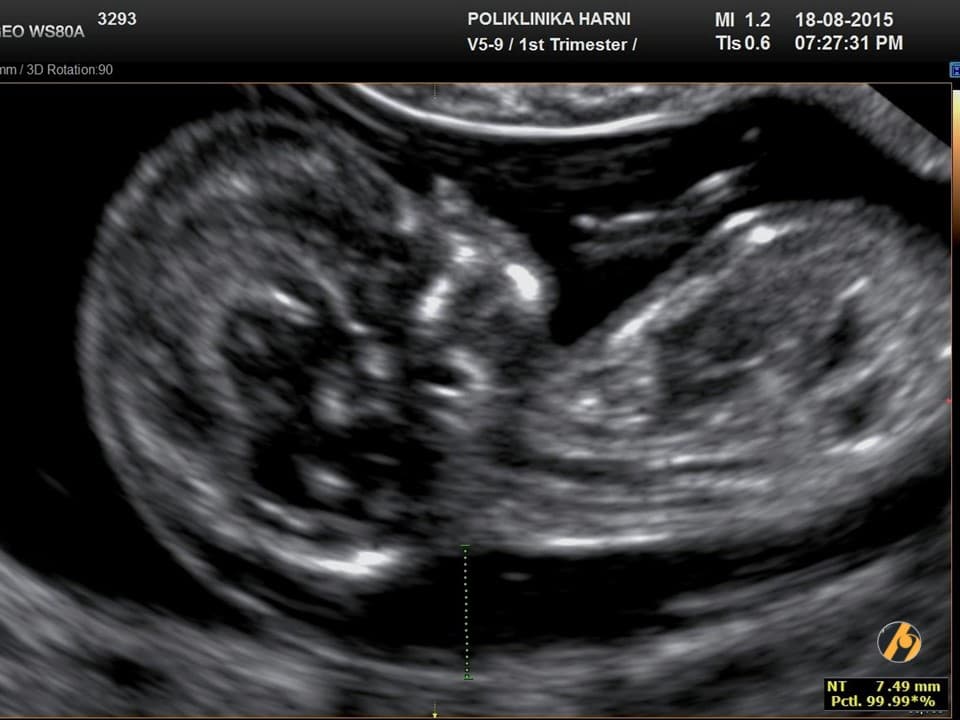

Trudnicama s povećanim rizikom ginekolog će preporučiti jedan od invazivnih testova – biopsiju korionskih resica ili amniocentezu radi potvrde definitivne dijagnoze. Najčešće kromosomske anomalije su trisomije 21, 18 ili 13, anomalije spolnih kromosoma (45, X, 47, XXX, 47, XXY, 47, XYY) i triploidije. Zajednička karakteristika mnogih kromosomoskih anomalije u prvom tromjesečju je povećan nuhalni nabor - nakupljanje slobodne tekućine ispod kože u predjelu stražnjeg dijela vrata. U kasnijoj trudnoći, svaka kromosomska anomalija ima uzorak karakterističan za svoj sindrom.

Ako postoji ultrazvučni biljeg kromosomopatija, procijenjeni rizik se može dobiti množenjem a priori rizika (na temelju rezultata probira) s omjerom vjerojatnosti specifične strukturne anomalije ili markera. Omjer vjerojatnosti za trisomiju 21 je oko 1 (a priori rizik se ne povećava u slučaju ciste koroidnih pleksusa, ehogenog endokardijalnog fokusa, blage hidronefroze i skraćenog femura) i oko 10 (postoji deseterostruko povećanje a priori rizika za nuhalni nabor, prenazalni edem i hipoplastičnu nosnu kost).